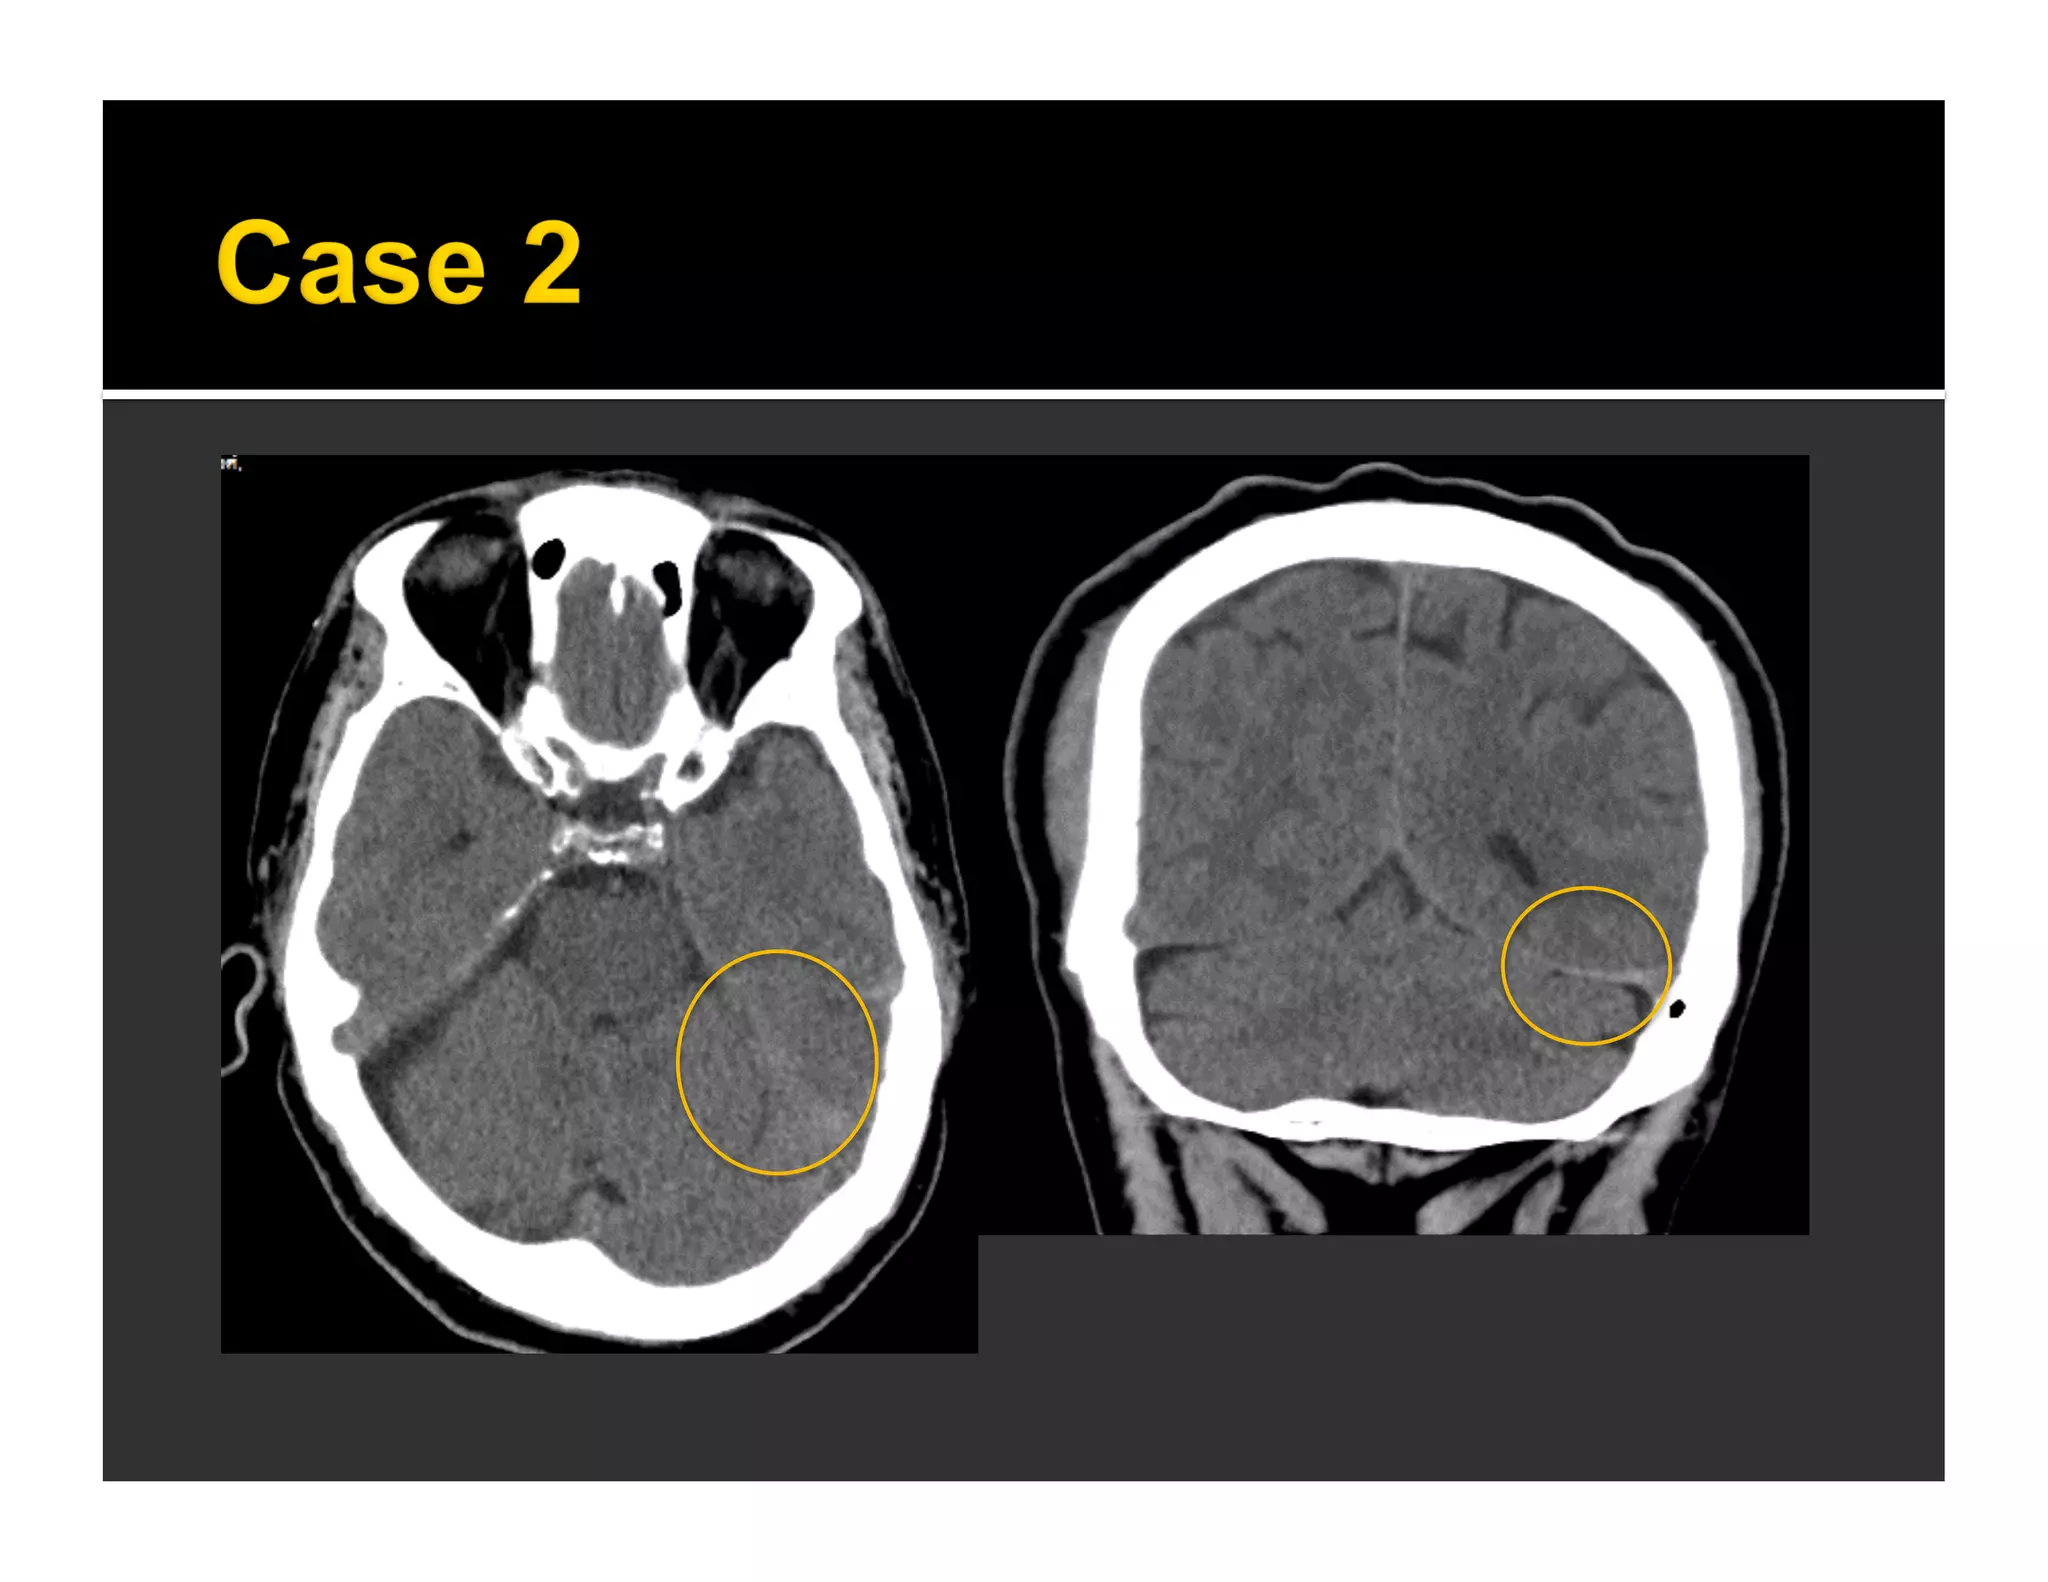

 EDH after and remote to decompressive

craniectomy (DC)

 Upon opening skull -- relief of tamponade

effect and hemorrhagic expansion of

injured meningeal artery, dural vein or

fractured diploe

 Evolve during operation

 May present during or after operation

 Can be fatal. Often need 2nd operation

 Su TM, et al. J Trauma 2008

 Case series of 12 patients

 Contralateral DEDH occurred after

decompressive craniectomy

 10/12 found to have contralateral calvarial fx

on preoperative CT

 12/12 found to have fx at surgery

 Talbott JF, et al. AJNR 2014

 Retrospective review of 203 patients who had

decompressive craniectomy for TBI

 6% had DEDH

▪ Age 32 +/- 13 years, two thirds had severe TBI,

mostly high impact injuries

▪ Time from sx to postoperative CT = 13 h

▪ All had contralateral calvarial fx on preoperative CT

at site of DEDH

 Large size (mean volume = 86 mL,

mean thickness = 2.5 cm)

 Mean midline shift = 10 mm

 Site of DEDH

▪ Contralateral to side of craniectomy

(10/12) and bilateral (2/12)

▪ All DEDH at site of calvarial fx

Contralateral skull fracture > 2 bones – 41 times to develop DEDH following DC

Talbott JF, et al. AJNR 2014

 Incidence 4.5-6.8% in patients with TBI

undergoing DC

 Predictor = contralateral calvarial fx

(esp. >2 bones involved)

 Surgeon should be alerted to

 Risks of intraoperative brain swelling

through craniectomy defect

 Need for early postoperative CT